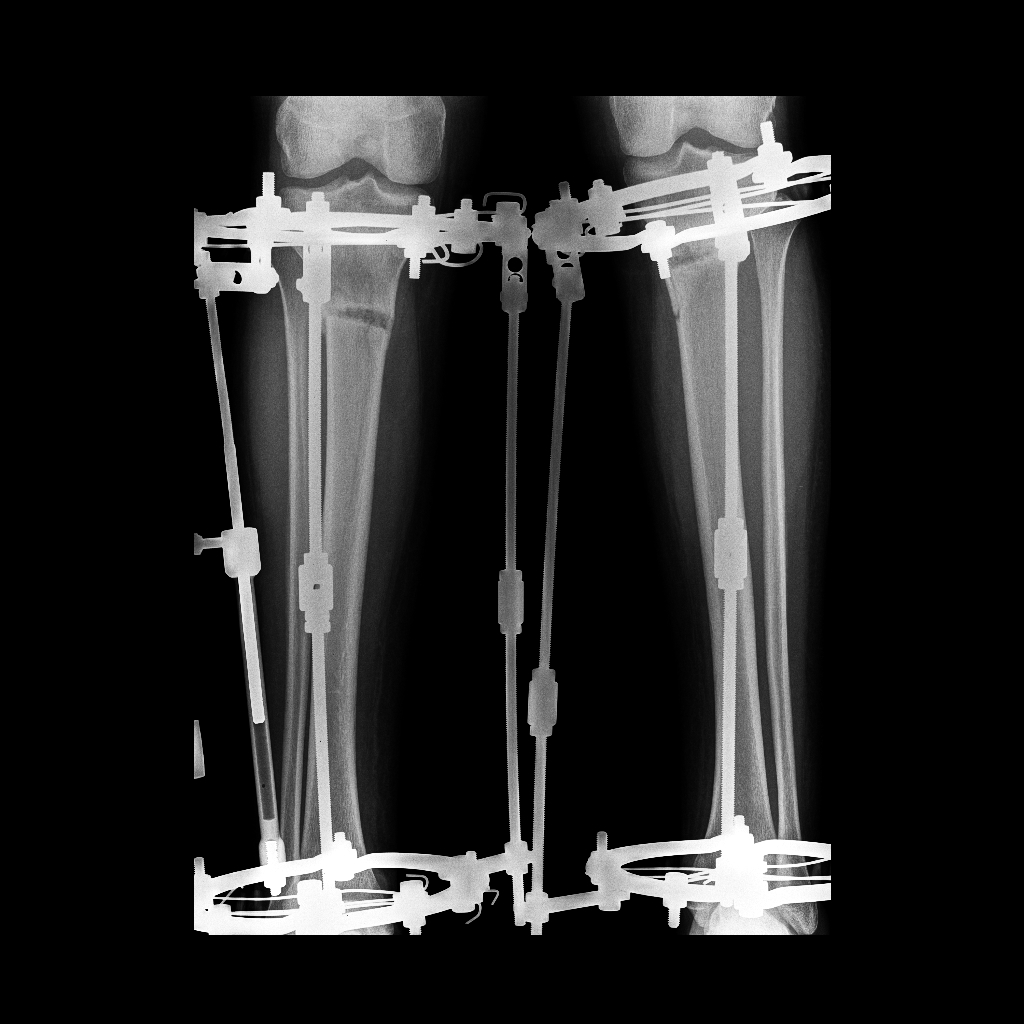

Исходник - 26 лет.

Дата операции 27.09.2016г.

РЕНТГЕН ДО ИСПРАВЛЕНИЯ ДЕФОРМАЦИИ

60 дней с момента операции.

Можно снимать аппараты joy , но мы подстрахуемся ещё на 2 недели bully !

60 дней.

Дата операции 27.09.2016г

Дата снятия аппаратов 15.12.2016г.

Срок лечения 73 дня.